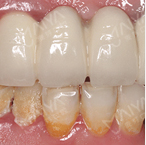

患者秀 爱美大概就是牺牲了半口好牙装上了烤瓷冠,结果一口烂牙再也救不回来了…来深圳种好了半口牙,终于像正常人一样吃喝了。

香港面包师郄女士

4675